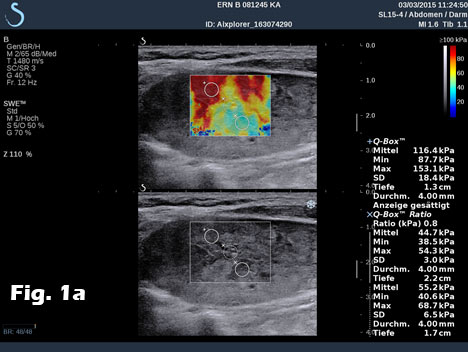

We report on the incidental finding of a 70 y/o patient presenting with an indolent cervical swelling and mass. Clinical examination and laboratory data were not conclusive. In the figure sequence B mode ultrasound and shear wave elastography revealed a 43 mm mass lesion with peripherally stiffer tissue (a) with thrombosis in statu nascendi of jugular vein shown by B mode (b) and also by contrast enhanced ultrasound (c) and shear wave elastography (d). 3D shear wave elastography confirmed the circumscript peripherally stiffer cervical mass (e). 3D SWE added complementary information for a better delineation of the distribution of increased stiffness, following the fibrous capsule around the nerve. SWE also showed feasibility to demonstrate stiffer tissue within jugular vein. 3D techniques allowed improved documentation of the anatomical volume including the tumour and surrounding vessels [(1-3)]. Histologically the nerve tumour schwannoma was proven.

Figure 1:B mode ultrasound and shear wave elastography revealed a 43 mm mass lesion with peripherally stiffer tissue (a) with thrombosis in statu nascendi of jugular vein (b), also shown by contrast enhanced ultrasound (c) and shear wave elastography (d). 3D shear wave elastography confirmed the circumscript peripherally stiffer cervical mass (e).